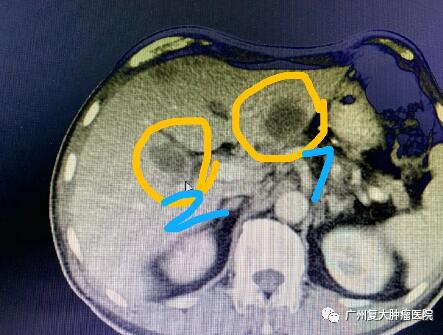

影像圖片顯示

圖3

為減輕腫瘤負(fù)荷,改善生活質(zhì)量,延長(zhǎng)患者生命,經(jīng)患者及家屬同意,我院牛立志院長(zhǎng)為其實(shí)行胰腺腫瘤、肝臟腫瘤不可逆電穿孔治療,術(shù)中以胰腺腫瘤、肝臟10個(gè)病灶為靶區(qū)消融。術(shù)后聯(lián)合化療加免疫藥物治療進(jìn)一步改善治療效果。